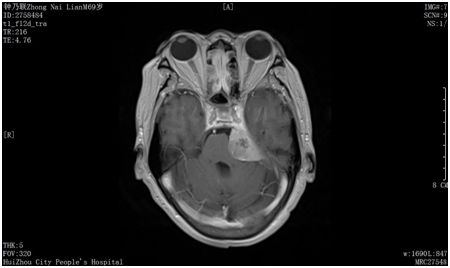

他只是一名普通的退休老人,十多年前被診斷為腦膜瘤(一種良性腫瘤),但是當時因害怕手術治療,而選擇了保守治療。腦膜瘤雖不至于威脅生命,但劉大爺卻因此不幸患上了繼發(fā)性三叉神經(jīng)痛,四處求醫(yī)仍不得治,一直痛到了現(xiàn)在。

文主任介紹:“根據(jù)劉大爺?shù)牟∏?,按常?guī)的治療思路來說,應該先開顱切除顱內(nèi)腫瘤,再治療三叉神經(jīng)痛。但是他不愿意接受開顱手術,又迫切需要‘止痛’。對于這種想止痛又不愿動刀子的患者來說,通過微創(chuàng)治療三叉神經(jīng)痛便再適合不過了,也就是三叉神經(jīng)微球囊壓迫術。

盡管該患者選擇接受三叉神經(jīng)微球囊壓迫術,但由于病情較特殊,手術較為復雜,難度較大。因為腫瘤長在麥克氏囊,可操作空間小,術中出血幾率高。再者患者年紀大,對手術醫(yī)生來說,是一個不小的挑戰(zhàn)?!?/span>

在C形臂引導下經(jīng)嘴角外側(cè)穿刺進入卵圓孔,將球囊導管送至半月神經(jīng)節(jié),充盈球囊,壓迫數(shù)分鐘,破壞神經(jīng)傳導,達到治療目的。